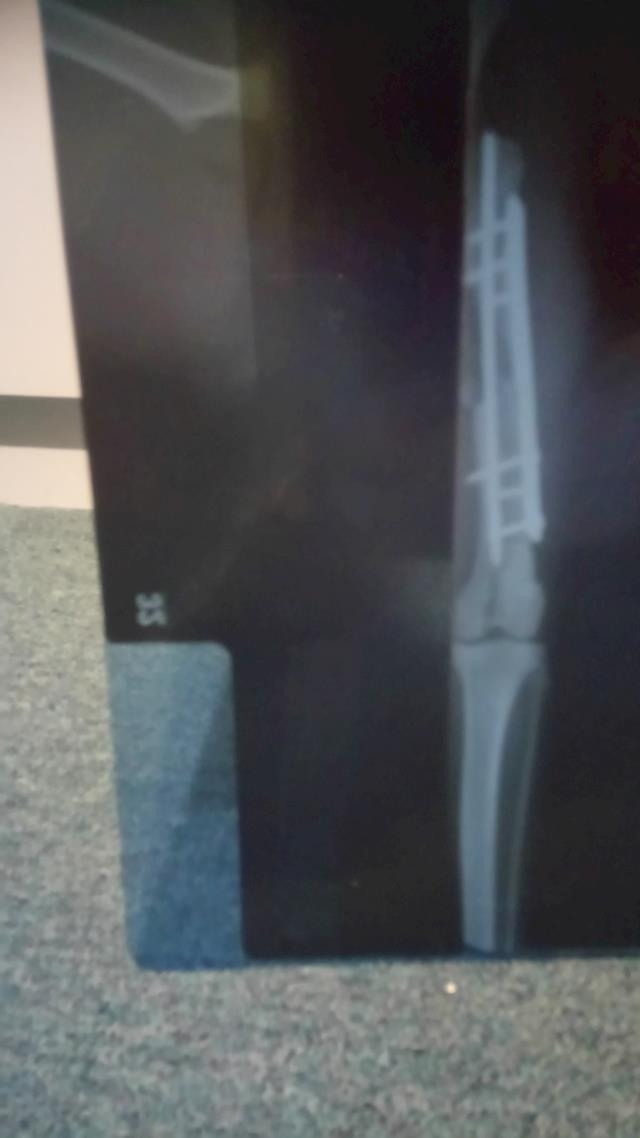

So here you can see the Rod they inserted into the middle of the bone and attached plates and screws to hold the bone in place.